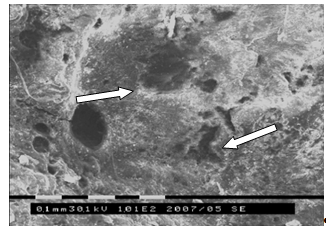

. Исследование морфологии огнестрельных переломов пластинчатых и

трубчатых костей методом сканирующей электронной микроскопии (50 образцов).

трубчатых костей методом атомно-силовой микроскопии (25 образцов).